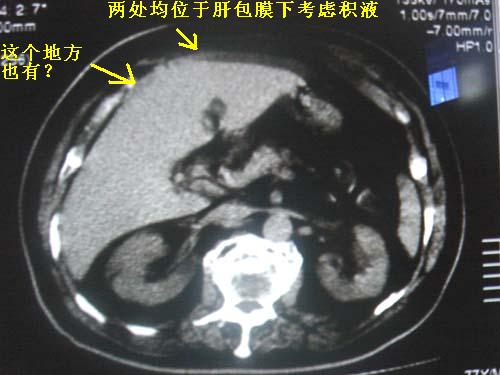

请大家看一下,肝左叶前缘低密度影考虑什么?只有这一层。

少量腹水? 包膜下脂肪?建议mr定性。

包膜下正常组织,并非积液.

测ct值,可能是伪影,脂肪组织,积液

经各位老师一说,我还真拿不准了,最好连续层面观察就能鉴别是否是膈肌及容积效应所致。细节决定成败,期待高手帮忙解惑!!!不过本人还是支持正常表现的。